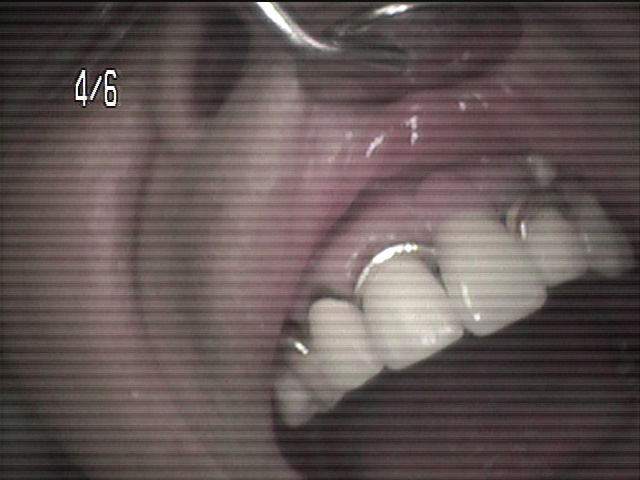

上の入れ歯がこわれてしまって、来院されました。のこっている上の前歯の6本分がつながったブリッジは歯ぐきが根元ではれていてぐらぐら状態。全く噛む場所がありません。

診断すると、残っている前歯4本は歯の中がほとんどくさってしまっていました。

残念ながら前歯はすべて抜かなくてはならず、上の歯は総入れ歯としてまず治療用入れ歯を事前に準備することから開始しました。同時に歯ぐきの腫れの消炎処置をしました。

前歯のつながった歯を切り離し、同時に歯を抜き、その日にすぐに仮の入れ歯を装着することとしました。

顎の粘膜の調整をしながら経過し、上の入れ歯との噛み合わせを調整していきます。

顎の状態が良好になってきました

約2ヶ月後最終入れ歯を入れた状態です。

初診から最終調整まで、前歯がなくなってしまう見栄えが悪い事は一日もなく治療を進行することができました。

現在 右も左もしっかりと噛む事が出来ます。